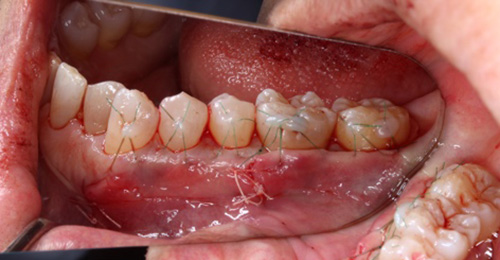

下顎の前歯4本の歯肉退縮治療

写真の上が治療前、下が治療後です。

前歯部4本を、VISTAテクニックにより、歯肉移植術を行いました。

歯肉退縮治療387,200円(4歯・税込)

歯肉が下がってしまった分すべてを回復できるわけではなく、どの程度回復できるかは、状態によります。プラークコントロールが良くない場合や、喫煙者では成功率が下がります。

治療期間

移植処置後、1〜2週間を目安に抜糸・消毒を行います。